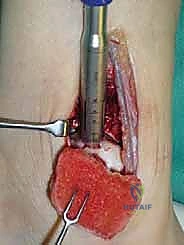

الغوص العميق: تقنية الزرع الغضروفي العظمي الذاتي (OATS) خطوة بخطوة

تُعد تقنية OATS (Osteochondral Autograft Transfer System) بمثابة "زراعة أعضاء دقيقة" داخل المفصل. الفكرة الأساسية هي أخذ أسطوانة صغيرة من العظم والغضروف السليم من منطقة لا تحمل وزناً كبيراً في جسم المريض (غالباً من مفصل الركبة)، ونقلها وزرعها في مكان الآفة التالفة في الكاحل.

هذه التقنية توفر "غضروفاً زجاجياً حقيقياً" (Hyaline Cartilage)، وهو نفس نوع الغضروف الأصلي الذي خُلق به الإنسان، مما يضمن متانة وقدرة على تحمل الأوزان لا يوفرها أي علاج آخر.